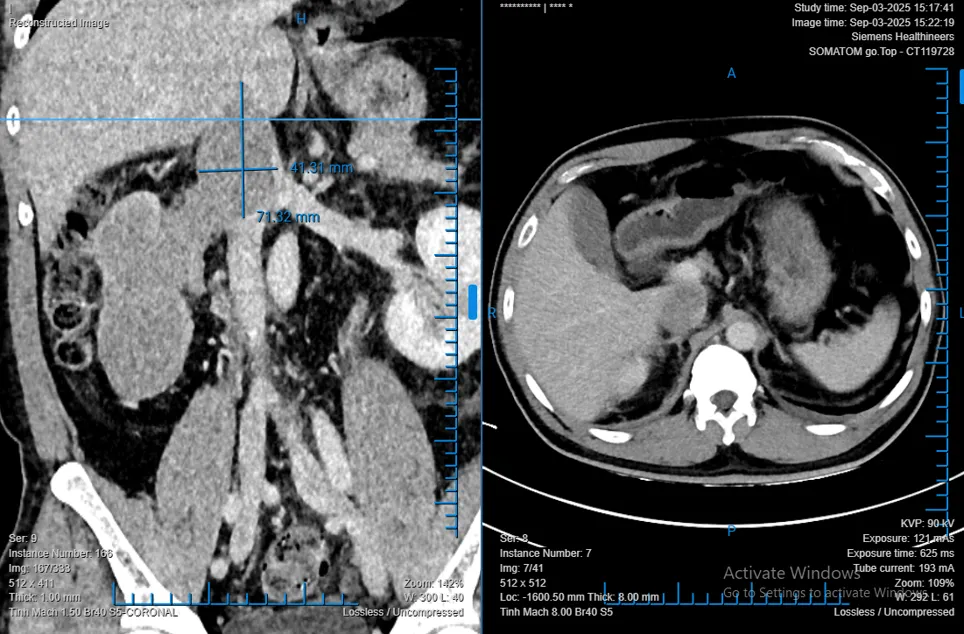

Người bệnh là anh T.D.L (48 tuổi, quê Quảng Trị), phát hiện khối bướu thận phải kích thước 68x86x138 mm, huyết khối bướu lan sâu vào tĩnh mạch chủ dưới. Nhận định đây là ca bệnh phức tạp, ekip 4 chuyên khoa gồm Tiết niệu, Gan mật, Tim – mạch máu và Gây mê hồi sức đã phối hợp phẫu thuật trong 8 giờ liên tục.

Khối ung thư biểu mô tế bào thận có huyết khối bướu - Ảnh: BVCC

Khoảng 4–10% bệnh nhân RCC có huyết khối bướu tĩnh mạch, từ độ I đến IV theo phân độ Mayo. Phẫu thuật cắt thận và lấy huyết khối bướu là phương pháp điều trị chuẩn được khuyến cáo bởi Hội Tiết niệu châu Âu (EAU). Nếu không được can thiệp, người bệnh dễ rơi vào suy tim, phù nặng hoặc tử vong. Tuy nhiên, đây là phẫu thuật khó, nguy cơ biến chứng tới 34% khi huyết khối lan đến tĩnh mạch gan, đòi hỏi ekip đa chuyên khoa và kỹ thuật cao.